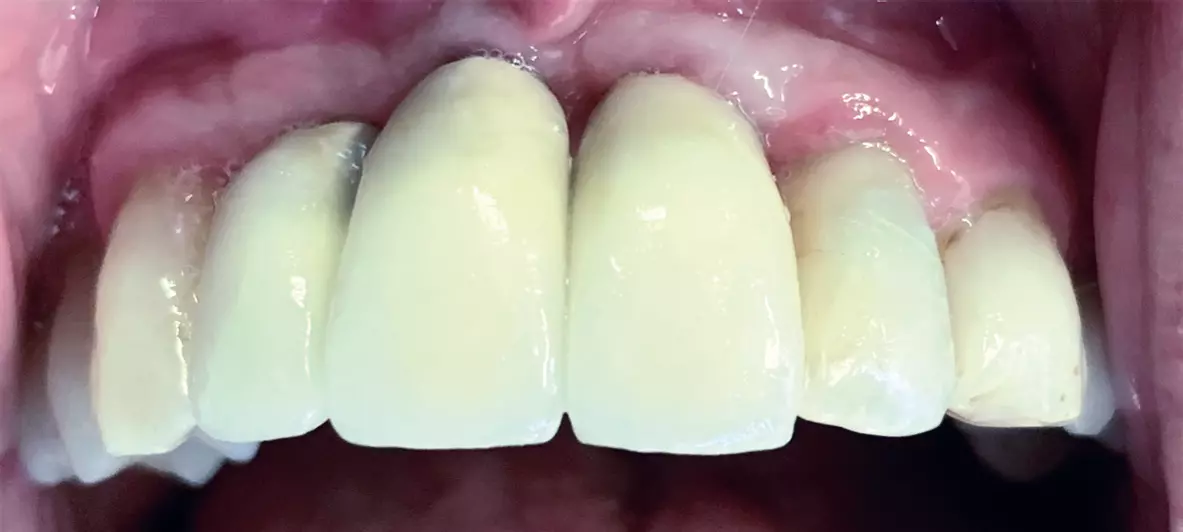

Im Frontbereich ist der Vorteil dieser Fixationsmethode darin zu sehen, dass keinerlei Schraubenzugänge zu verschließen sind, was der Ästhetik und der sensiblen Taktilität der Zunge zugutekommt (Abb. 9a-d).